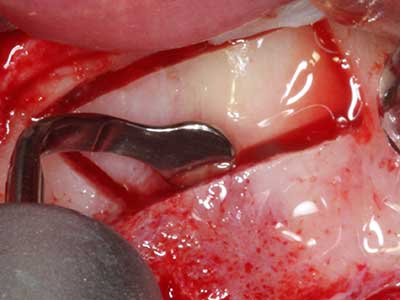

En la extracción de bloques óseos la piezocirugía también presenta ventajas adicionales: Además de la alta precisión en la osteotomía que ya se ha descrito antes, se ha comprobado que el uso de los delgados insertos de sierra resulta especialmente cuidadosas con el hueso. Frente a esto, sobre todo cuando se usan las fresas de Lindemann, cabe esperar pérdidas en la extracción significativamente más altas debido al mayor grosor de la parte frontal del cabezal (Lakshmiganthan, Gokulanathan et al. 2012). La separación basal que se necesita en particular en los injertos de bloque extraídos de forma retromolar se ve facilitada mediante sierras perpendiculares especialmente previstas a tal fin, lo que permite considerar que la cirugía piezoeléctrica es un procedimiento preciso y seguro para la obtención de bloques de hueso en el área retromolar (Happe 2007) (fig. 1-12).